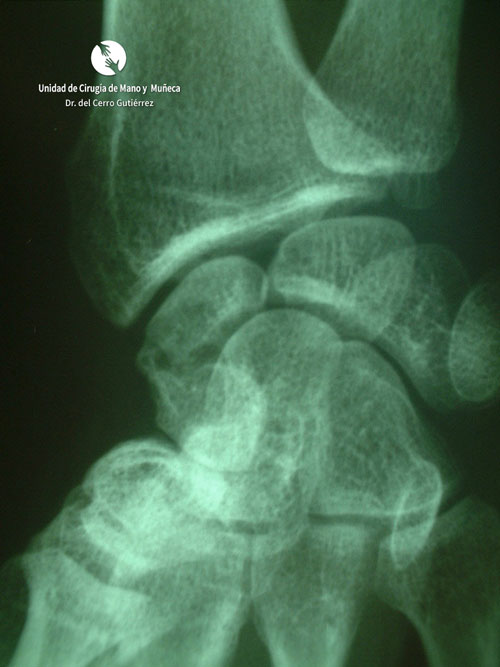

Pseudoartrosis. Inestabilidad Dorsal del Segmento Intermedio. DISI

Fractura del escafoides. Pseudoartrosis del tercio medio